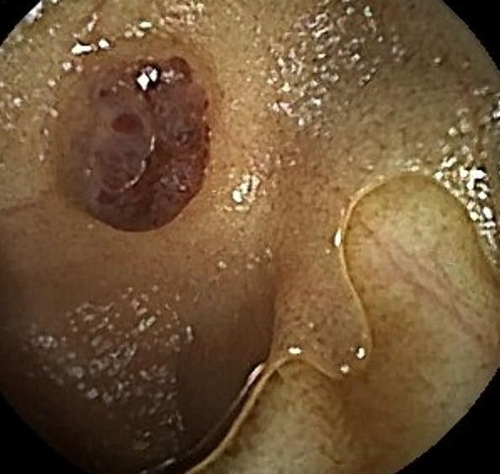

為了進一步查找病因,兒童消化內(nèi)科醫(yī)生決定利用“胃鏡+結(jié)腸鏡+膠囊內(nèi)鏡”三鏡聯(lián)合的方式進行檢查。檢查結(jié)果觸目驚心!

浩浩的胃、小腸及結(jié)腸內(nèi)有多發(fā)藍色大皰樣隆起,大大小小的有20多個,就好像在胃腸內(nèi)灑落了許多藍莓。尤其是小腸病變尤其明顯,最大顆幾乎堵塞了腸腔的一半。

兒童消化內(nèi)科急請血管瘤診療??茖<視\,結(jié)合既往病史,最終診斷為“藍色橡皮皰痣綜合征”。這些藍色大皰樣隆起其實是消化道靜脈瘤,間斷有靜脈瘤破裂出血,浩浩的重度貧血正是由于本病引起的長期消化道慢性出血所致。至此,困擾浩浩一家長達2年之久的反復(fù)貧血之謎得以解開。